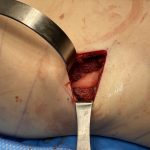

Plastic Surgery Case Study – The Location of The Pleura in Rib Removal Waistline Narrowing Surgery

Background: One of the considerations in rib removal surgery is the location of the lung. Anatomically they extend from just above the clavicle down to the 6th rib in the front and the 10th rib in the back…which is where we are most interested in rib removal surgery. It is also relevant to note that Read More…